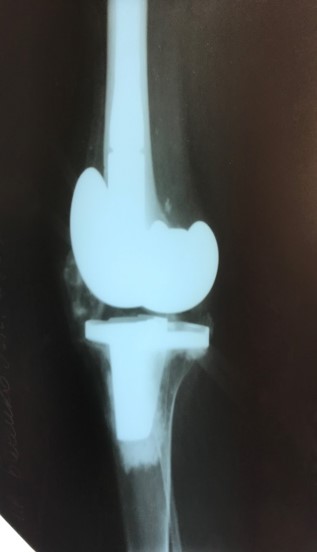

Приклад 4. Хвора Г. 72 років. Діагноз: Деформівний IV ст. гонартроз, стан після ТЕП КС (2010р.). Гемартроз в післяопераційному періоді, хронічний синовііт.Септична нестабільність компонентів ендопротеза  колінного суглоба на протязі року. Виявлений дефект виростків стегнової кістки  тип Т3, F 3 за класифікацією АОRI [G.A. Engh, C.H. Rorabeck, 1997]. Хворій виконано  двоєтапне ревізійне ендопротезування: видалення компонентів ендопротезу іплантовано спейсер з антибіотиком. Піcля санаціїї виконано другий єтап певізії, імплантовано ревізійний ендопротез колінного суглоба.